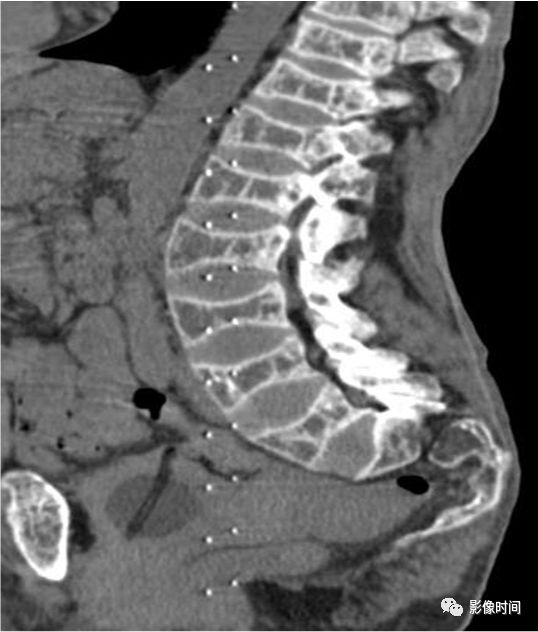

10栅栏征

栅栏征(The Palisade sign),也称灯芯绒椎体(corduroy vertebra)或灯芯绒征(corduroy sign)

脊椎椎体因病变导致骨小梁吸收、稀疏,为满足承重需要,存留的纵向骨小梁粗大;粗大骨小梁间以细条状密度减低区,形成栅栏样影像,故称栅栏征或灯芯绒椎体。

栅栏征最常见于血管瘤,以单个脊椎居多;骨质疏松如泛发性骨质增生症、老年性骨质疏松等亦可呈现此类表现,一般见于下胸椎、上部腰椎的多个椎体,只是伴有普遍的骨密度减低。有时自颈椎至腰椎全部椎体均出现栅栏征。栅栏征主要见于椎体。

典型病例

病例 1,脊柱血管瘤。胸腰椎 CT 冠状位、矢状位 MPR 重建示胸 12 椎体松质骨密度降低,其中可见粗大骨小梁呈栅栏状。